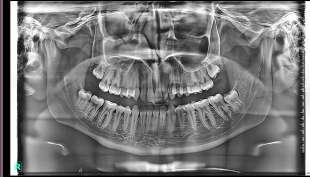

Elevate your 2D panoramic imaging with Deep-View AI, the revolutionary technology that enhances every detail with unmatched clarity and precision.

• Sharper images for superior diagnostics

• Enhanced contrast and depth to reveal critical details

• AI-powered optimization for faster, more efficient processing

Powered by advanced neural networks and deep learning, Deep-View AI processes X-VIEW 2D PAN and X-VIEW 3D PAN images with unparalleled accuracy. This cutting-edge technology unveils hidden anatomical

structures, optimizing every pixel in real time for precise and confident diagnostics.

Developed by Trident, this AI-driven enhancement is redefining the standards of dental imaging, setting a new benchmark for clarity and efficiency.